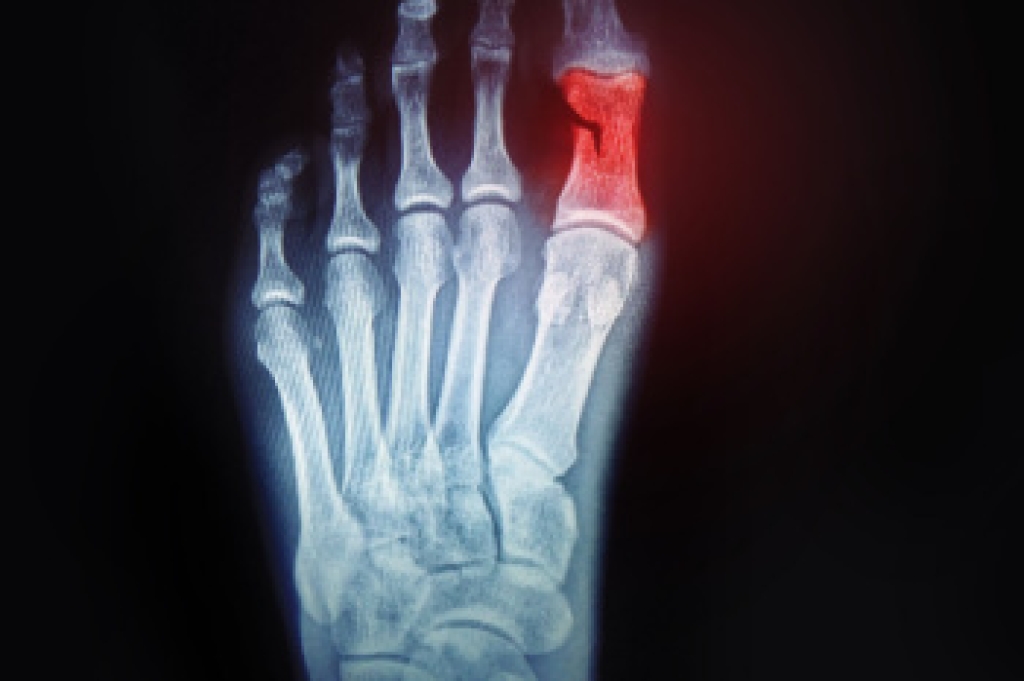

Foot and ankle injuries are a common occurrence when it comes to athletes of any sport. While many athletes dismiss the initial aches and pains, the truth is that ignoring potential foot and ankle injuries can lead to serious problems. As athletes continue to place pressure and strain the area further, a mild injury can turn into something as serious as a rupture and may lead to a permanent disability. There are many factors that contribute to sports related foot and ankle injuries, which include failure to warm up properly, not providing support or wearing bad footwear. Common injuries and conditions athletes face, including:

- Ankle Sprains

Sports related injuries are commonly treated using the RICE method. This includes rest, applying ice to the injured area, compression and elevating the ankle. More serious sprains and injuries may require surgery, which could include arthroscopic and reconstructive surgery. Rehabilitation and therapy may also be required in order to get any recovering athlete to become fully functional again. Any unusual aches and pains an athlete sustains must be evaluated by a licensed, reputable medical professional.